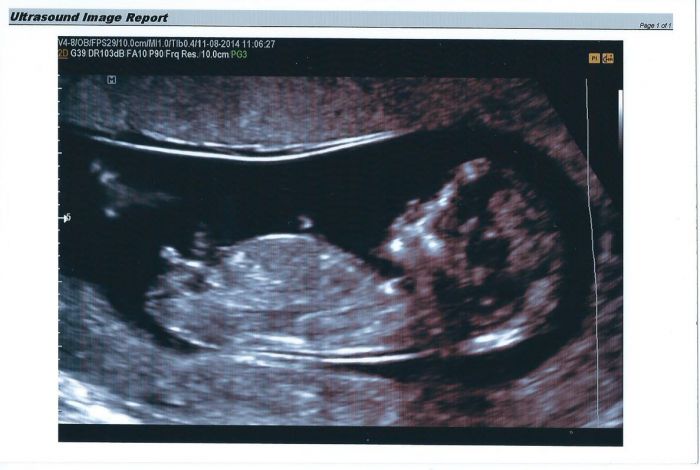

Ahoj holky tak jsem zpet a jsem zdravíííí a kraaasny a mame kluka :) asi tak na 100%..:D pridavam fotku a je to na nni pekne videt mu to tam trci s pritelem jsme se tomu museli smat i sestricka se smala ze to bylo rychle urcene ani se nas nezeptal jestli to chcem vedet :D :D ... Pan doktor mi pomalu ani neprilozil utz a uz hlasil ze je to kluk :D bylo to kraasne videt ...:o) Mam raadost neskutecnou ... Jinak je to mrnousek ale s tim jsem pocitala kdyz jsem nejedla zadny vitaminy a i kyselina listova sla vzdycky ven takze je broucek malinkej ma 6,4 cm :)